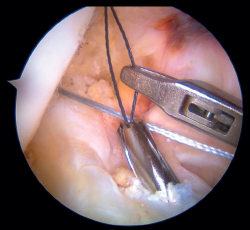

Figura 4. Perforación con punzón en la pared medial del cóndilo femoral externo para posterior colocación del implante sin nudos en la técnica de fijación femoral con implante. Rodilla izquierda, visión desde el portal anterolateral.

Figura 5. Fijación de suturas en el cóndilo femoral externo mediante implante sin nudos (SwiveLock®, Arthrex). Rodilla izquierda, visión desde el portal anterolateral.